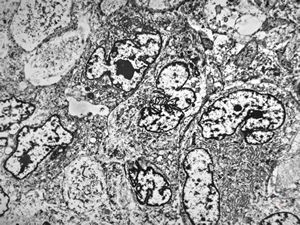

F,25y. | myopathy - atrophic and regenerating muscle cells

M,2y. | myopathy - regenerating muscle cell